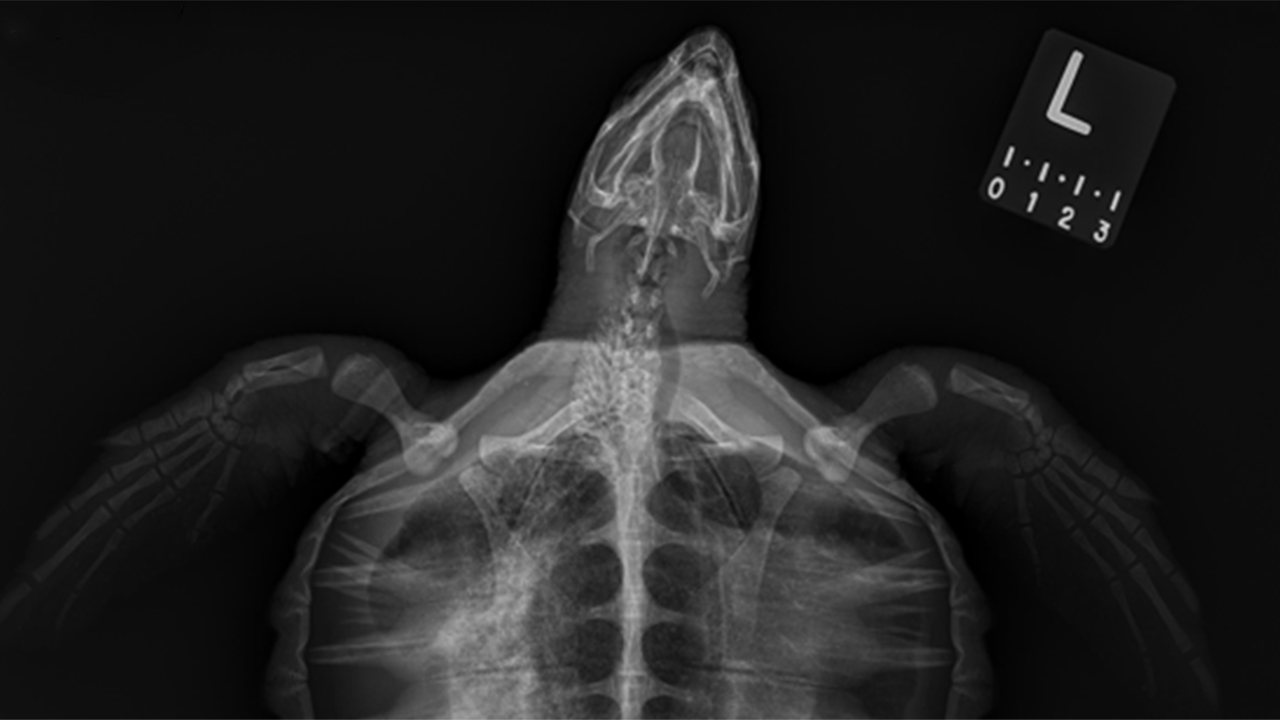

What It’s Like Working at the Aquarium’s Sea Turtle Hospital

From cold-stunning season to long-term rehabilitation, a senior biologist shares what it takes to rehabilitate injured sea turtles.